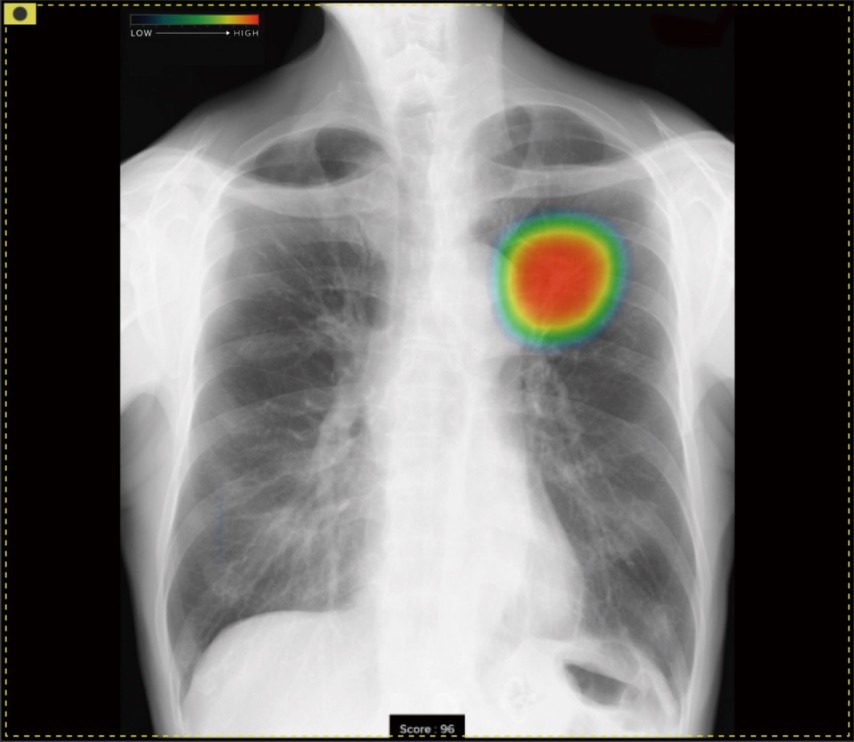

当院では、AI(人工知能)による最新の『X線画像病変検出ソフト』を導入しています。これは胸部X線(レントゲン)画像をAIが解析し、肺炎や肺がんなどの病変を高精度に検出できるシステムです。

特に肺がんは初期症状に乏しく、発見が遅れると進行しやすいため、定期的な検査による早期発見がとても重要です。このシステムは、最新の技術(ディープラーニング)を活用し、過去の膨大な医用画像データを蓄積して学習を重ねています。そのため、人間の視覚だけでは捉えにくいような異常な陰影も、AIが補助的に検出することで、診断の精度を大幅に向上させることができます。AIの結果はあくまで「補助診断」であり、最終的な診断は医師が行いますが、より安全で精度の高い医療の提供につなげることができます。

病変の存在が疑われる領域を検出・マーキングします。